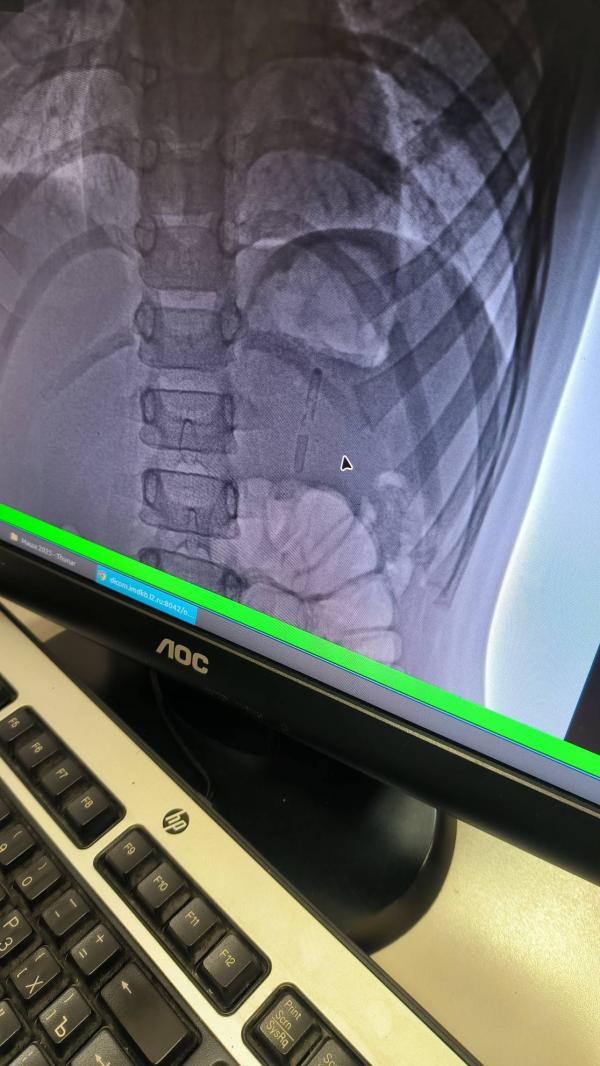

Это светящиеся палочки,они были как трубочки для сока, вдохнул ее и проглотил

Чтоб само вышло ,а если нет то вытаскивать смотря куда пройдет,тоже их не поняла ,если на 10 см пройдет то фгдс,если чуть дальше полостная ,а ещё дальше колоноскопия.Лучше бы сразу убрали